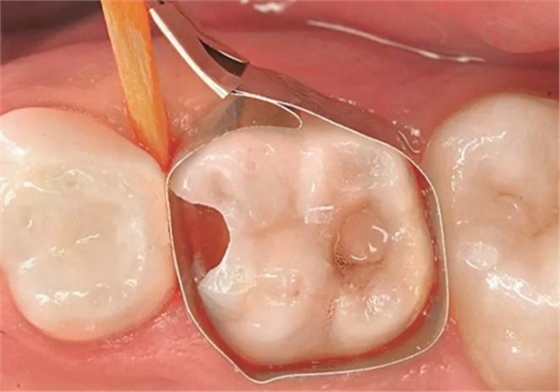

圖4:64號乳牙去腐后,放置一個T型成行片和一個木楔

圖5:用Prime&Bond NT (Dentsply De Trey) 處理窩洞,作用時間為20秒,然后輕吹至少5秒并光固化10秒